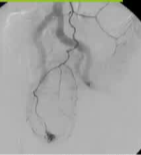

· 可考虑Angiography and embolization(血管造影 + 栓塞):介入放射科通过导管超选至出血血管,进行栓塞止血

·Angiography(血管造影)

o即使血流动力学稳定,若高度怀疑动脉性出血,仍可行血管造影

血管造影

·优势:血管造影(尤其是CT血管成像或数字减影血管造影)对活动性出血(造影剂外溢速率≥0.5 mL/min)的定位准确,且可同时进行超选择性栓塞止血。